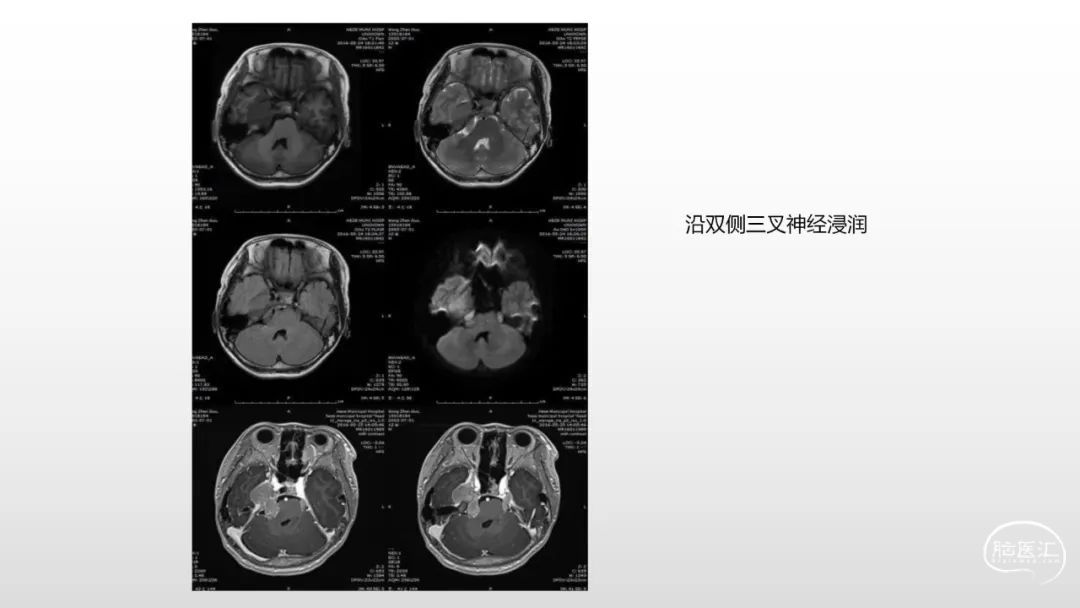

颅脑影像诊断基础知识讲座:脑膜病变